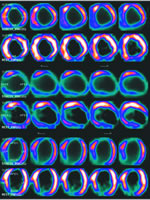

患者,65岁,男性,临床诊断扩张型心肌病。经序贯性诊断程序诊断为缺血性心肌病(图1~3),最终建议进行外科CABG或心脏移植手术治疗。

图1 CT-CA示3支病变,左前降支(LAD)、右冠状动脉(RCA)中远段闭塞

图2 腺苷负荷MPI示左室前壁、心尖部可逆性灌注缺损